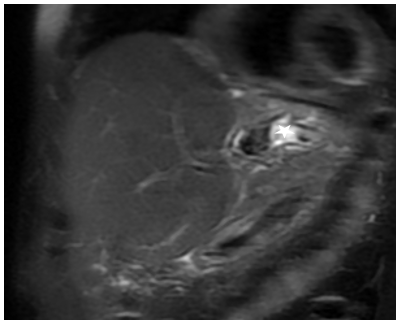

Ultrasonography showed a suspicious left hepatic duct stone with a dilated common bile duct and left biliary radicals. A contrast enhanced computed tomography scan of the abdomen and pelvis demonstrated an atrophic left lobe with multiple hypodense liver lesions suggestive of stones, particularly in segments II and III, with the largest measuring approximately 4 cm, likely representing a liver abscess with a cluster sign due to recurrent pyogenic cholangitis (Figure 1). MRCP confirmed evidence of a dilated left intrahepatic bile duct with multiple stones, associated with edema of the left liver lobe, findings consistent of oriental cholangiohepatitis. The common bile duct was dilated with multiple small stones (Figure 2). Patient underwent ERCP using Spyglass that failed to opacify the Left IHBR by to complete obstruction of the LHD due to giant stone. CBD clearance was performed with plastic stent insertion (Figure 3).

Figure 2. MRI liver image showing stones, dilatation and edema (Cluster Sign), in a segment II bile duct (star).